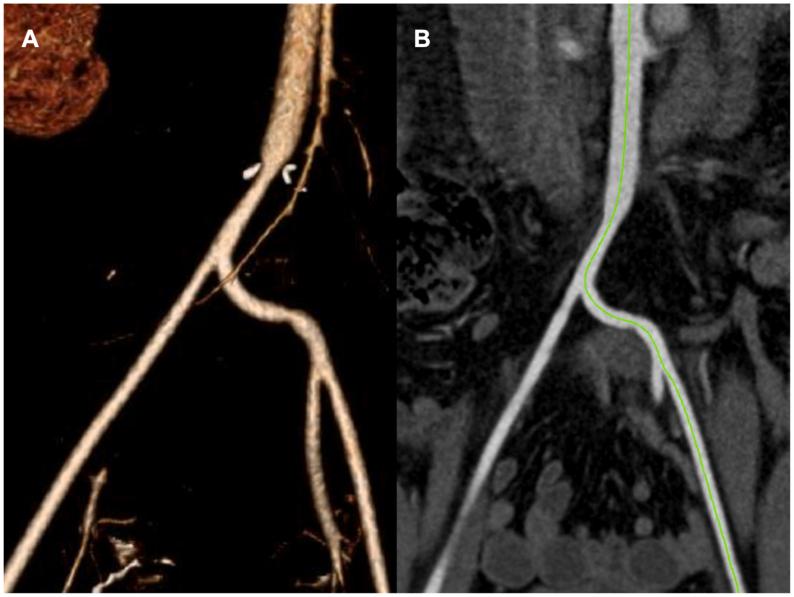

Blunt abdominal aortic injuries, especially in pediatric patients, represents a rare and critical challenge. We report a unique case of a 10-year-old boy who presented after a high-speed motor vehicle collision resulting in injury to the aortic bifurcation, alongside other intra-abdominal trauma. A novel surgical approach for aortoiliac reconstruction in a contaminated field was used. This technique consisted of the mobilization of the distal aorta and common iliac arteries, ligation of right internal iliac artery, and creation of aortoiliac and common to internal iliac artery anastomoses. This method demonstrates a potentially lifesaving technique in select patients.

钝性腹主动脉损伤,尤其是在儿科患者中,是一种罕见且严峻的挑战。我们报告了一例独特的病例,一名10岁男孩在高速机动车碰撞后出现,导致主动脉分叉损伤,同时伴有其他腹部创伤。我们采用了一种在污染区域进行主髂动脉重建的新颖手术方法。该技术包括游离远端主动脉和双侧髂总动脉、结扎右侧髂内动脉,以及创建主髂动脉和髂总动脉至髂内动脉的吻合口。这种方法在特定患者中显示出一种可能挽救生命的技术。